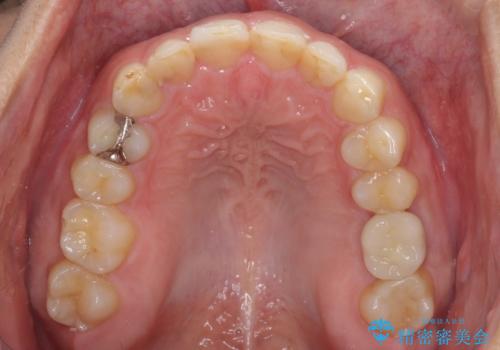

- 深い咬み合わせと前歯のデコボコ、奥歯の欠損を気にして来院された患者様です。

歯列矯正はインビザラインを使用し、矯正治療中の適切な時期に奥歯の欠損部位にインプラントを埋入することとしました。